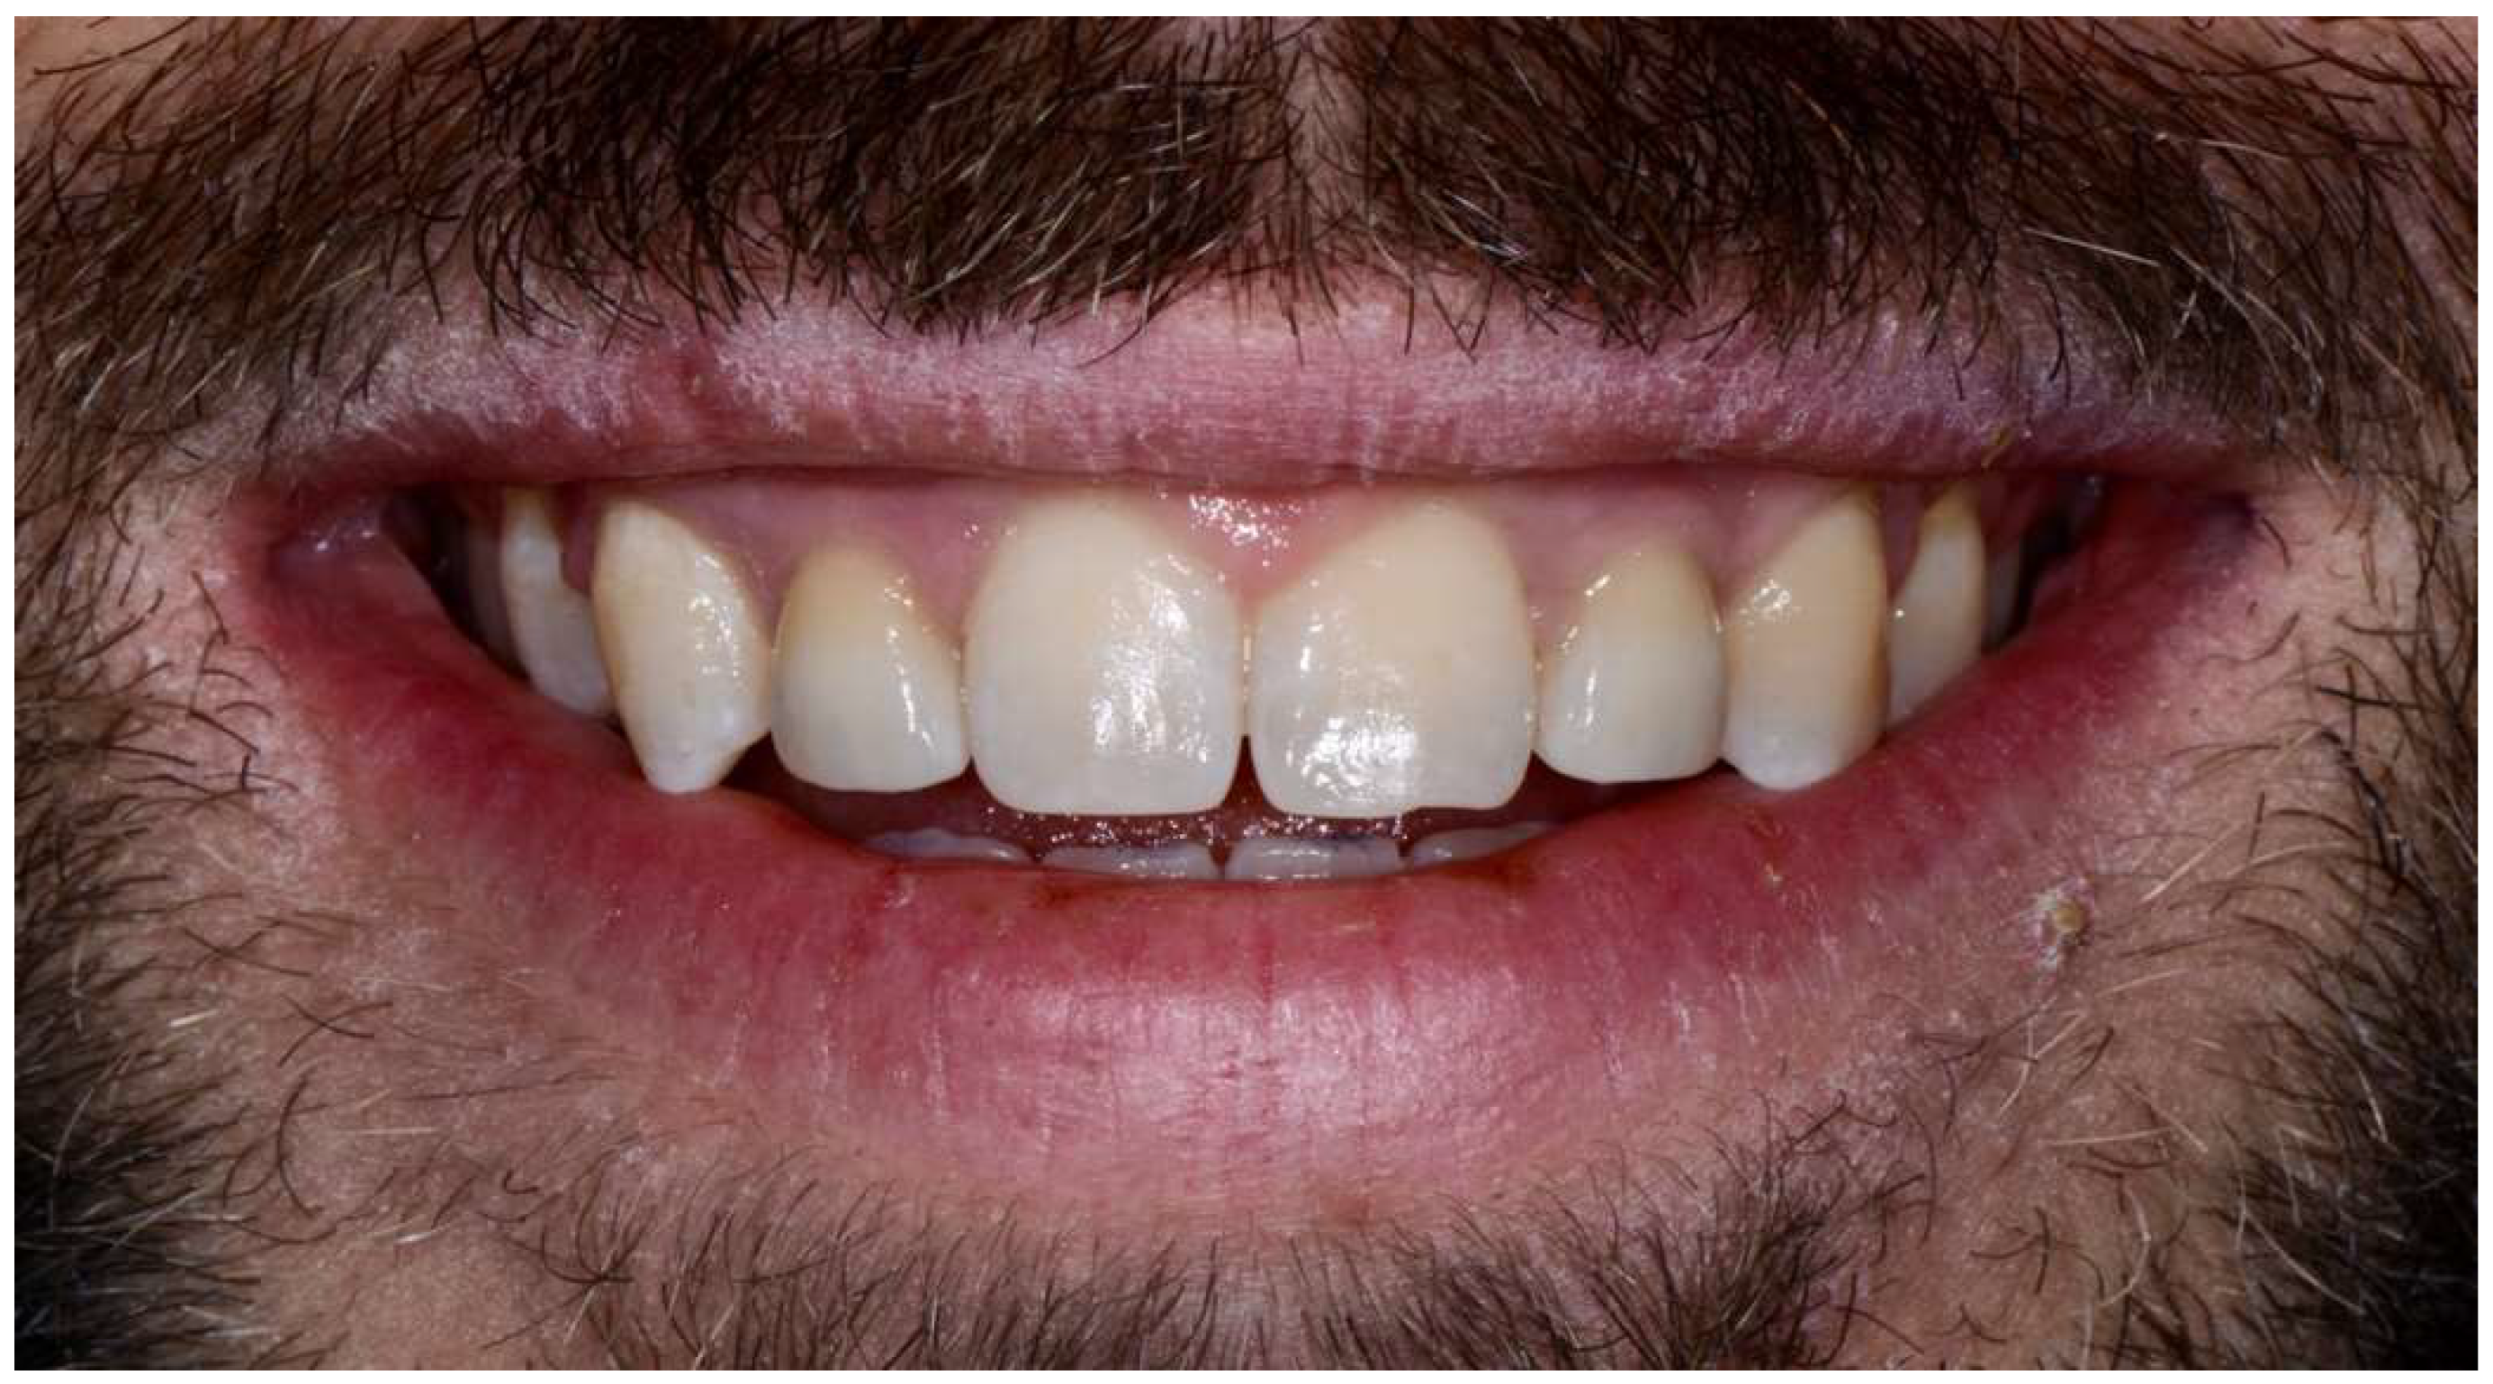

- 11–12 months: prosthetic finalization and baseline control (T0);

- appearance of the crown (margin and color);

3. Results